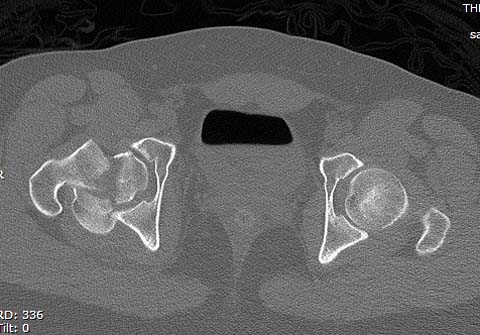

Здесь клинические примеры: Первый случай передний доступ, второй с ICP

monitor Flipp Trochanteris

и с переломом заднего края.